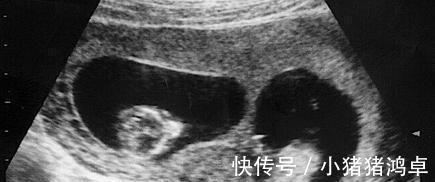

怀胎十月一朝分娩,在很多人的印象中只要到了产房,孩子很快就能出生,不过这也仅限于正常的一个胎儿,但要是两个及以上的胎儿,有可能就会出现分两天出生的情况。

胡女士是一位38岁的高龄孕妈,非常幸运的是,虽然是高龄孕妇,但是怀的却是龙凤胎,这可让全家高兴坏了,一次怀俩,儿女双全这是多少人梦寐以求的事情了。

由于是两个孩子,到了孕晚期的时候全家都做好了要早产的准备,果不其然胎儿在30周的时候就开始发动了,丈夫赶紧带妻子去医院,经过诊断后,胡女士确实是要生了。

医生连忙准备手术,在经历几个小时的分娩,胡女士生下了一个女儿,就在陈女士想要一鼓作气把儿子也生出来的时候,被医生告知子宫硬已经停止收缩,如果继续可能会有危险,需要延期分娩。

每个胎儿都有自己的一个房间,两个孩子就有两间房,并且之间互不打扰,因此才会出现一个孩子出生之后,产妇宫口关闭的情况,在这种情况下为了胎儿的安全着想,一般医生都会停止手术,继续待产。